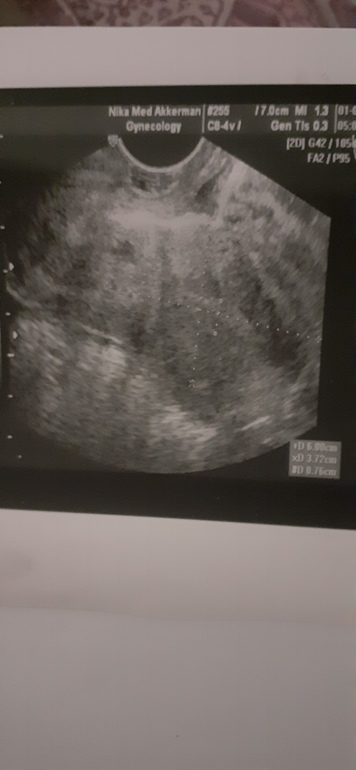

Помогите с результатами УЗИ

Цикл 40 - 42 дня. СПКЯ. Тест сегодня слабоположительный, но я не особо верб в реагенты, сделала потому что руки чесались. Вчера была на УЗИ, врач сказал, что все хорошо и при таких показателях может прикрепиться плодное яйцо ХГЧ сдам послезавтра, если м не придут .

Желтое тело и жидкость говорит о прошедшей овуляции. Тепепь ждите месячных, если пойдут, то жт с ними выйдет. Не пойдут, згачит зародилась новая жизнь

Маловато. Должно быть 20мм

Ну, вы же понимаете, что овуляция была. ЖТ есть, эндик не плохой (( Я забеременела на 6,5)) Так что ваш тест может и не реагент показал, а начало...)))